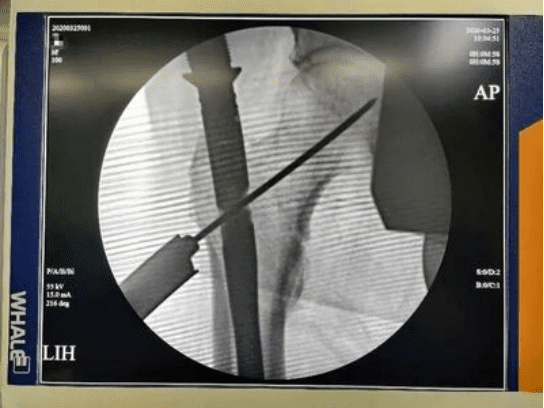

A 100-year-old male patient presented to the hospital with right hip joint pain and limited mobility, symptoms that had persisted for five days following a fall. After admission, the patient was diagnosed with a right intertrochanteric fracture of the femur. Due to the patient’s age, Dr. Cheng fully demonstrated the case, combining the actual situation of the patient with anesthesia in collaboration with related departments, decided to choose the Tri-max nail for minimally invasive closed reduction and internal fixation of fractures for surgical treatment, and formulated a meticulous surgical plan.

The whole operation was very smooth, and it took less than 30 minutes for the skin incision to suture. On the first day after the operation, the patient achieved early mobilization of the affected limb, and on the third day, the patient got out of bed. Canwell Tri-max with excellent mechanical design to help patients quickly recover. This operation effectively avoided the complications caused by conservative treatment and created good conditions for the recovery of limb function.